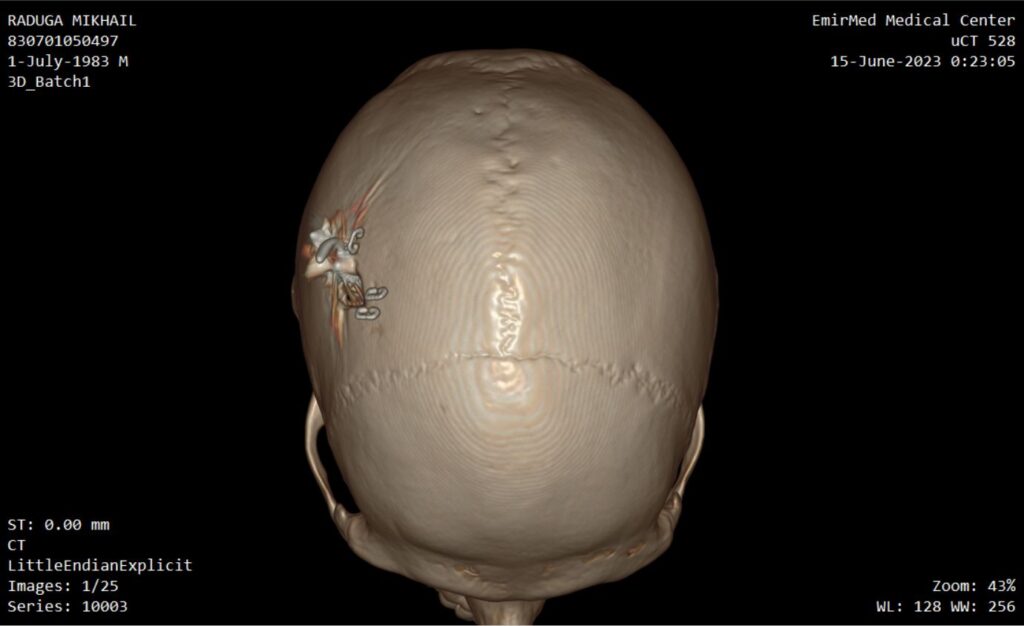

Implant

Device for electrical stimulation

Photos of computed tomography